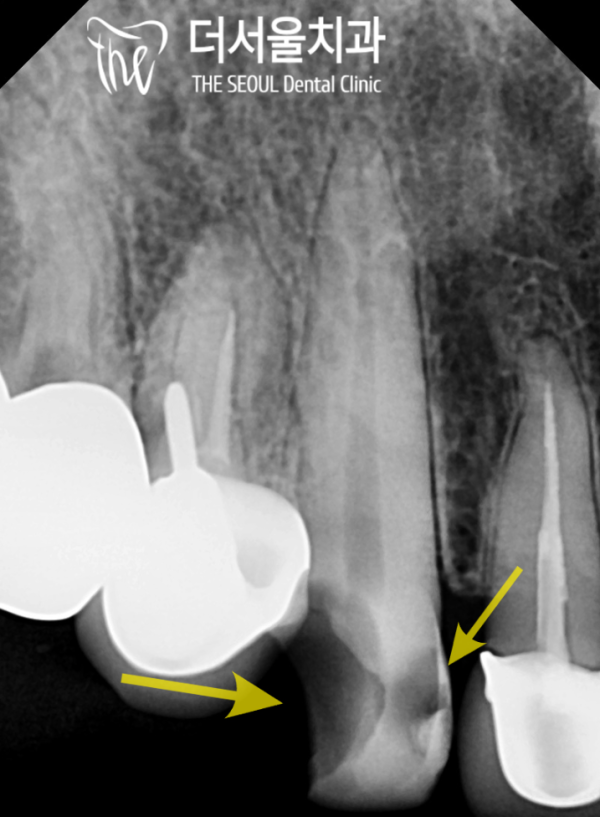

엑스레이 사진으로 파절이된 부위를 보면 치관 대부분에

우식이 퍼져있습니다.

거의 절반 가까운 파절이 일어났기 때문에

신경치료와 임플란트중에서 고민하게되었습니다.

If you look at the broken part of the crown with an X-ray

Woo-sik is spread out.

Almost half of them were broken

I was torn between nerve treatment and implantation.

이런경우에는 이미 심한 손상이 있고, 우식이 넓게 퍼져있기 때문에

어디까지 진행되었는지 알수없어서 신경치료가 쉽지 않았지만

보존과전문의가 있는 성남치과 더서울치과에서는 이러한 고난이도의

케이스도 잘 치료를 해 나갈 수 있습니다.

In this case, there's already severe damage and the beef cattle are spread out

Neurotherapy wasn't easy because we didn't know how far it went

Seongnam Dental Clinic The Seoul Dental Clinic, where there is a conservation specialist, has this difficulty

The case can also be treated well.